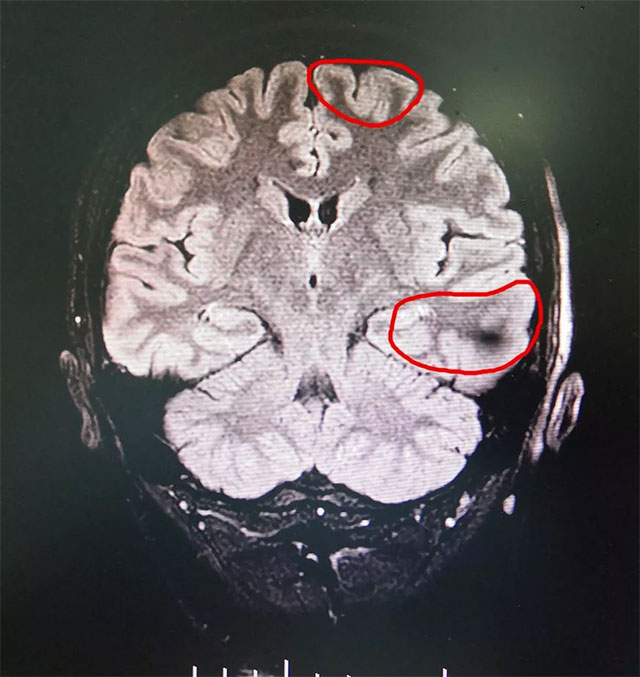

▲ 综合MR、24小时视频脑电等多种检查,最终确定患者癫痫病灶

经过检查,患者经系统内科药物治疗不佳,确诊为难治性癫痫。MRS示双侧海马结构异常,PET-CT显示左侧大脑代谢下降,VEEG检查可见异常波:左侧大脑明显异常,大量癫痫波,结合患者病史并综合相关检查最终确定癫痫病灶位于左侧大脑(额颞海马)。